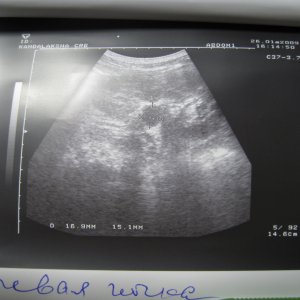

Доктор здраствуйте! мне 23 годаОколо полугода назад лежал на обследовнии в нефрологии,где был посиавлен диагноз:хр,пиелонефрит обеих почек,МКБ,микролиты обеих почек 2-4мм,наиболее крупный справа 4 мм!Было рекомендовано:курсам пить пролит,цистон,урологические сборы и тд!Все ето я принимал,почки особо не беспокоили если тока изредка небольши тупые боли в пояснице по утрам и все!Вчера решил сделать узи почек:диагноз был поставлен следующий:гидронефроз правой почки 1 степени,(врач сказал что лоханка в правой почке увеличена до 40 мм из за МКБ,лоханка левой почки 18 мм,остальные параметры в норме)микролиты обеих почек 2-4 мм,хр,пиелонефрит обеих почек!!количество мочи в течении дня нормальное,удалось сдать анализы мочи(общий и по Нечипаренко!Общий:

Чувствую себя нормально,небольшая слабость,утомляемость а так более менее!посоветуйте что нужно и можно делать в моей ситуации!какие препараты следует пропить и тд!урологов в городе нет,буду ждать ваших рекомендаций!файл с узи приложил